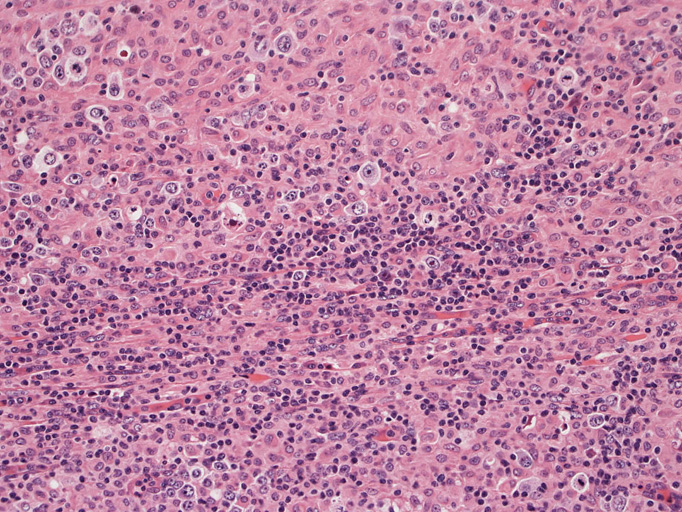

病理組織所見†

頸部リンパ節病理組織所見

直径17mmの腫大したリンパ節。被膜は軽度線維性肥厚を示す。リンパ節の基本構造は失われ不明瞭な結節様構造が集蔟しているように見える。

光顕および免疫染色所見

結節構造内では, 好酸性細胞質をもつ組織球の増生を背景に大型異型細胞が散在性または集蔟して増殖している。被膜下にも線維化組織内にbizzarreな大型細胞が認められる。リンパ球は小型リンパ球が大型異型細胞を含む組織球性の結節辺縁に存在する。大型細胞は, centroblastic cellが多く, その他 Hodgkin cell-like cell, RS細胞様巨細胞, 腎臓型の核をもった細胞, 多型核の細胞など多彩な形態を示す。異型核分裂像をふくむ核分裂像が多い。